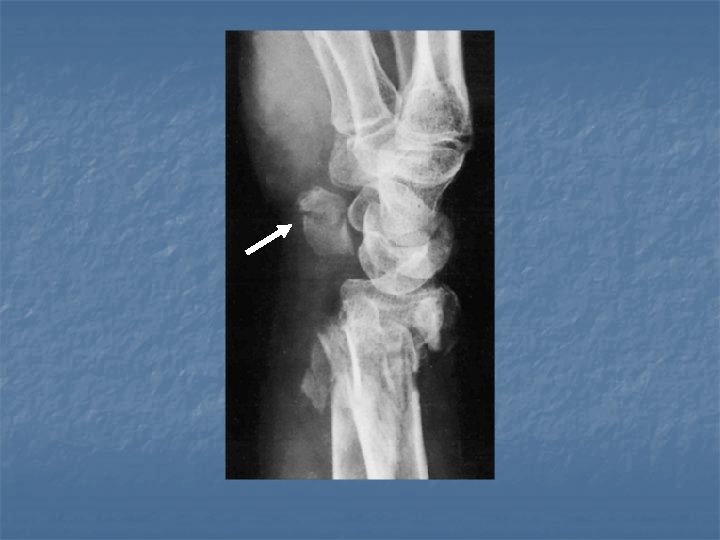

Fracture of triquetral n n Usually a subtle fracture Best seen in the lateral or pronated oblique view.